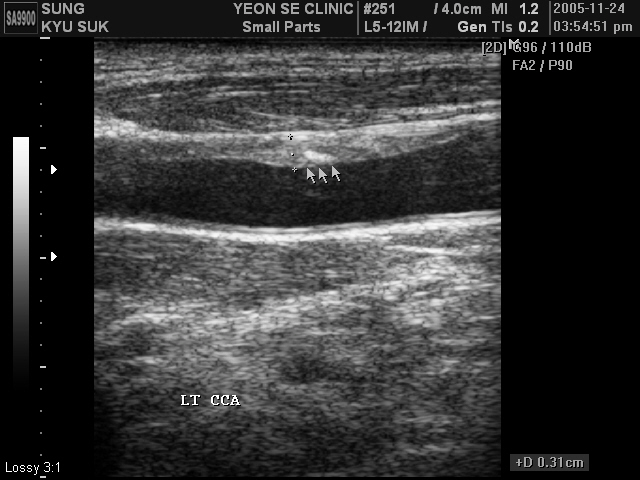

Ultrasonographic data of our patients

Carotid at...